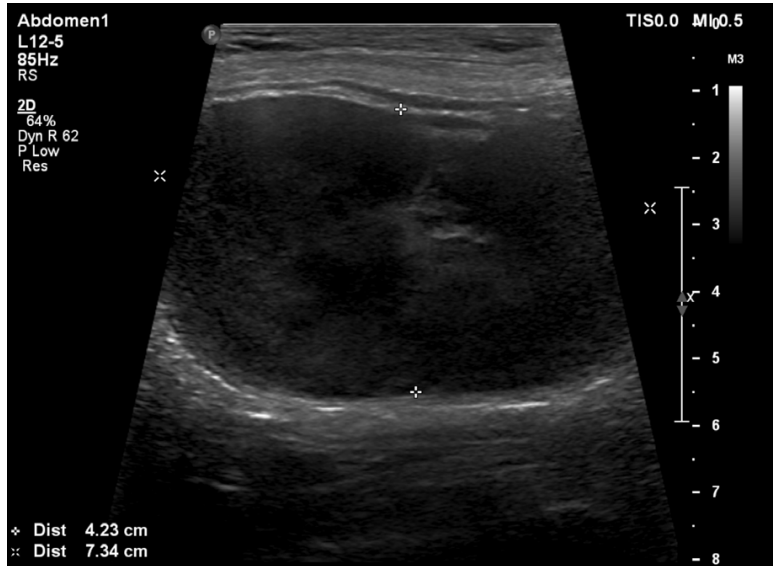

What is shown in this image?

A

uterine mass

-between the plus signs